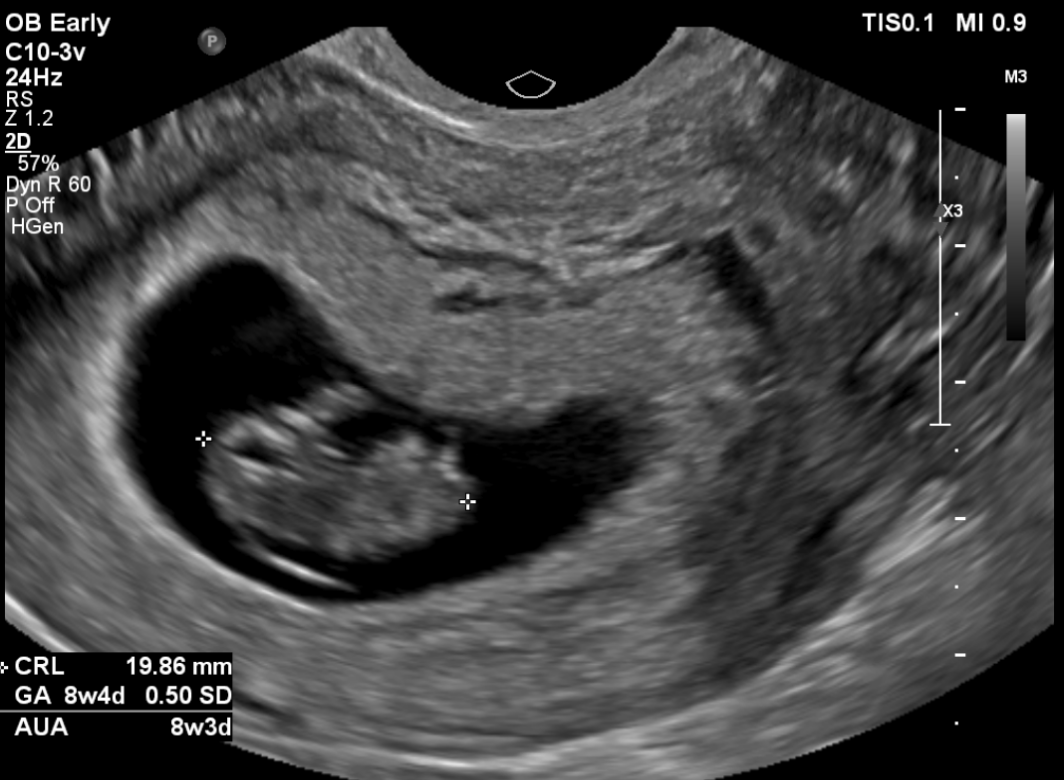

임신 8주 차 초음파 검사 ( 8주 5일 차 초음파 사진)

첫 트롱이 사진 짜잔~~ 젤리곰 이다 >. < 주수에 맞게 잘 자라고 있는 트롱이~ 심박수도 176 bpm으로 정상!

사실 초음파 검사 당시엔 아기 모습을 보지 못했어요~ 검사해주는 분께서 화면으로 보여주지도 않고 아무 말 없이 혼자 보면서 검사를 하시더라고요~ 그래서 저희 남편만 화면으로 확인하면서 너무 귀엽다고 잘 자라고 있다고 ㅠㅠ 저를 안심시켜줬습니다.

검사가 끝나고 전 메일로 받은 초음파 사진으로 처음 우리 아이를 봤어요~! 보고 나서 너무 귀엽고 제 뱃속에 이 작은 생명이 있다는 게 너무 신기해서 울었어요~ ㅜ.ㅜ~ ㅋㅋㅋ